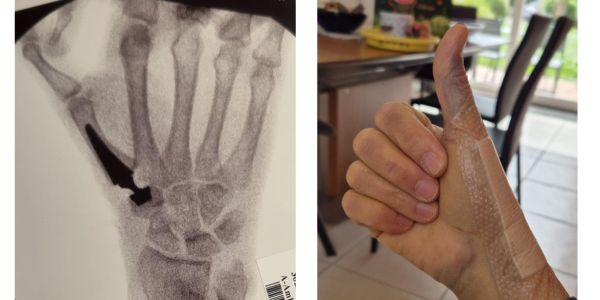

La rhizarthrose, ou arthrose du pouce, atteint l’articulation située à la base du pouce (articulation trapézo-métacarpienne). Elle provoque des douleurs chroniques, une perte de force, et gêne les gestes du quotidien comme tourner une clé, porter un sac ou ouvrir un bocal.

Après l’intervention, une orthèse post-opératoire est souvent prescrite pour immobiliser le pouce et favoriser la cicatrisation. Elle peut être portée pendant 3 à 6 semaines selon les cas. Dans cette période, l’objectif est de limiter la douleur, d’éviter les mouvements brusques et de prévenir les complications. Un œdème ou une certaine raideur peuvent persister temporairement : ces symptômes sont courants et ne doivent pas inquiéter.